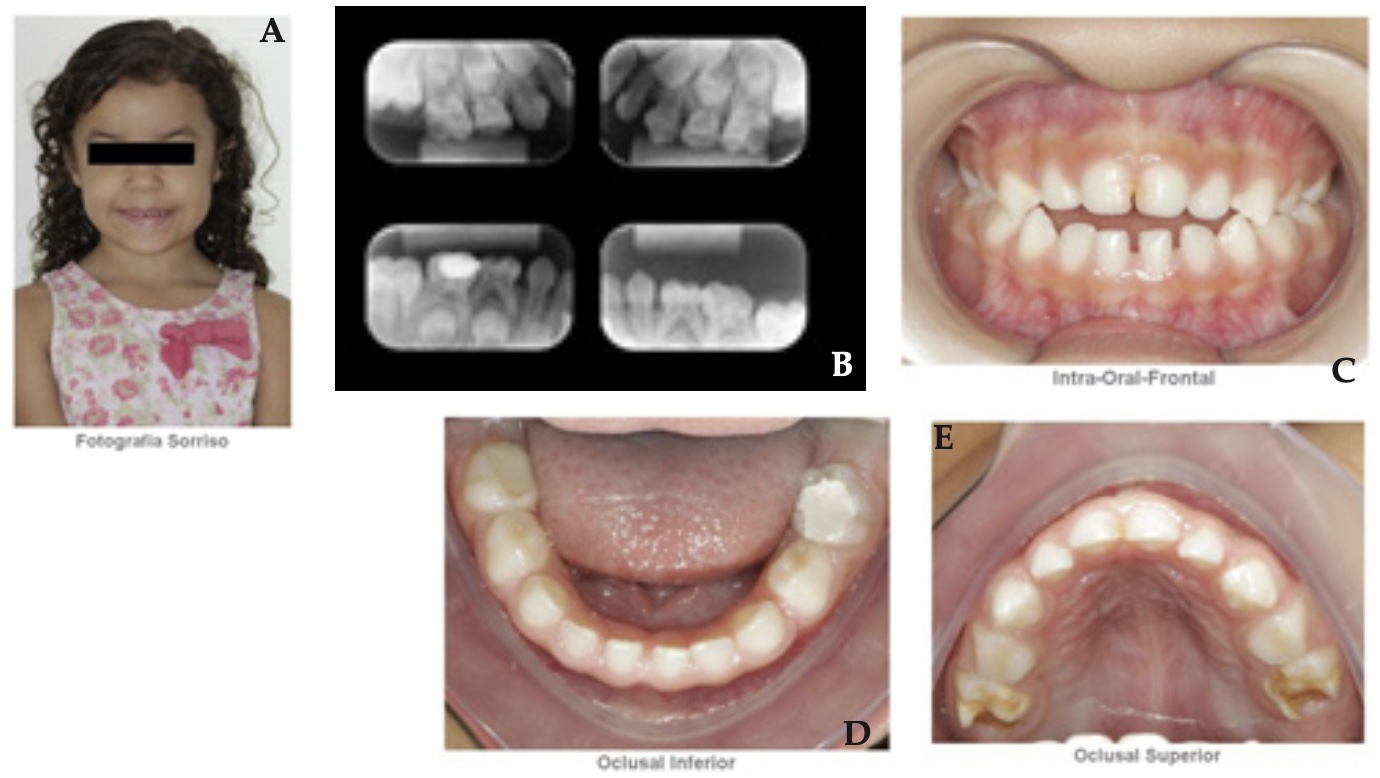

Ha sido estudiado el caso de dos niñas de 5 años, gemelas, univetelinas idénticas que poseían el mismo patrón de HMD en los dientes 55,65, 75 y 85, que ya se encontraban con alto grado de destrucción. En la gemela 1, se ha constatado lesión de caries en los dientes 85, 75 y 65 (Figura 1). Por otra parte, en la gemela 2, la lesión se concentraba en los dientes 55 y 65 (Figura 2). Además, se observó en ambas gemelas un histórico de sensibilidad en los dientes 55 y 65, seguido de incomodidad provocada durante el cepillado de dientes. Se observó, también, que la destrucción coronal en los segundos molares superiores de las niñas era consecuencia de las fracturas con la exposición dentinaria y acumulación de biofilm que ocasionan lesiones cariosas.

Figura 1: Gemela 1, una imagen clínica y radiológica sacada al iniciar el tratamiento. Se observa: en la imagen A, la fotografía de la sonrisa; la imagen B, radiografías periapicales; en la figura C, imagen vestibular de los dientes superiores e inferiores; en las imágenes D y E muestran la situación intrabucales de las superficie oclusales de las arcadas inferiores y superiores. Además, se ve los dientes 75, 85, 55 y 65 con hipomineralización.